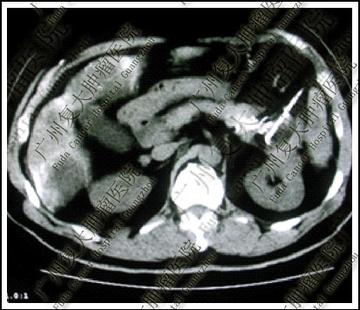

王家三口平時經常出現吃飯前後肚子痛的狀況,一開始都當作腸胃小毛病沒放在心上。直到有天兒子體重狂掉,從原本60公斤左右一路降到45公斤,這才緊急衝醫院檢查。結果醫師發現他的胰臟長出腫塊,血液數值也不正常,確診為胰臟癌。醫師表示,持續的腹部疼痛加上體重急速下降,都跟體內腫瘤逐漸變大有關。